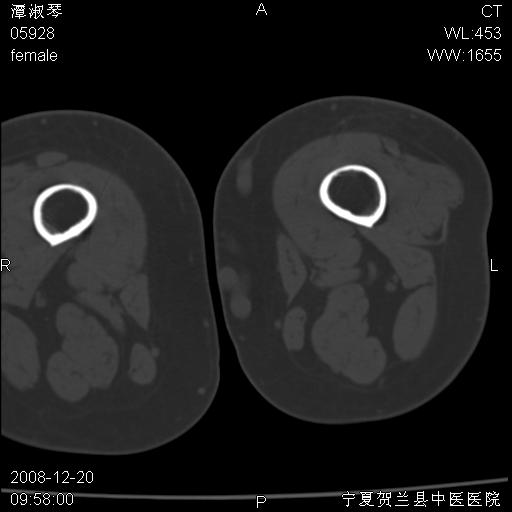

标题: CT17526:请各位看看是啥? [打印本页]

标题: CT17526:请各位看看是啥?

内生软骨瘤?骨梗死?

考虑内生软骨瘤可能性大

考虑-----骨梗死+退变

支持骨梗死,退行性骨关节病,膝关节积液.

考虑骨梗死可能性大

左股骨下段骨梗死。双膝退变。

左胫骨下端松质骨及髓腔内可见点片状高密度灶,骨皮质无明显膨胀及变薄。病变范围较长。支持骨梗死,退行性骨关节病,膝关节积液